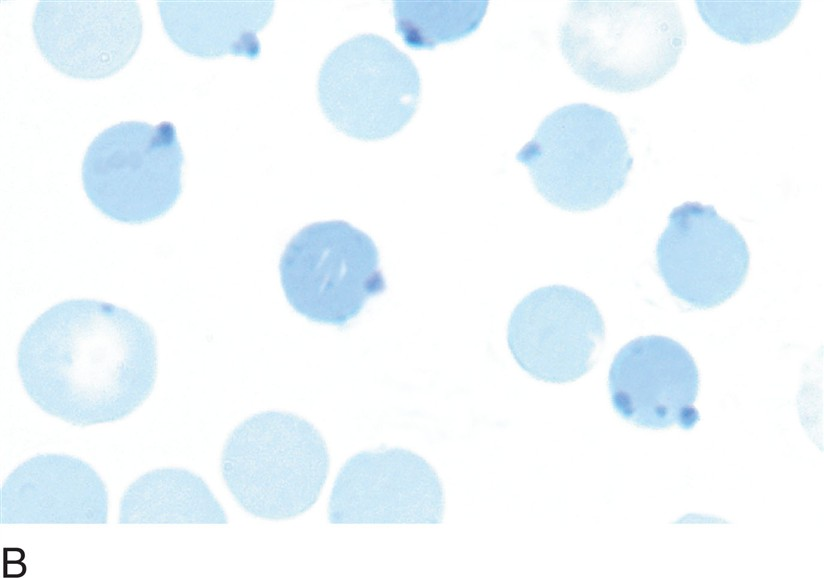

what hemoglobinopathy is this?

hemoglobin C disease